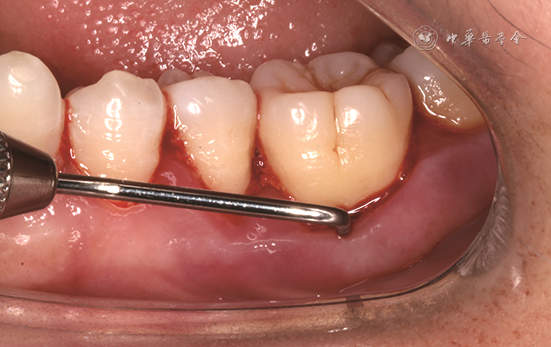

根分叉病变的诊断主要根据探诊和影像学检查。由于根分叉区的解剖结构特点,临床医师需使用特殊弯曲的根分叉探针——Nabers探针进行临床探诊。探诊时将Nabers探针置于根分叉入口冠方牙面上,再将探针以Z字形向根方移动,若探针可探及根分叉凹陷处,则为检测到根分叉病变(图1)。影像学诊断中,X线片对诊断根分叉病变有较大意义(图2),但二维影像学技术受投射角度及组织影像重叠影响,仅可提示根分叉病变的存在可能,必要时需借助锥形束CT进一步完善影像学检查[12, 13](图3)。